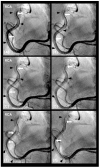

Background: In the study of coronary artery disease, the mechanisms underlying atherosclerosis initiation and progression or regression remain incompletely understood. Our research conceptualized the cardiovascular system as an integrated network of pumps and pipes, advocating for a paradigm shift from static imaging of coronary stenosis to dynamic assessments of coronary flow. Further review of fluid mechanics highlighted the water hammer phenomenon as a compelling analog for processes in coronary arteries. Methods: In this review, the analytical methodology employed a comprehensive, multifaceted approach that incorporated a review of fluid mechanics principles, in vitro acoustic experimentation, frame-by-frame visual angiographic assessments of in vivo coronary flow, and an artificial intelligence (AI) protocol designed to analyze the water hammer phenomenon within an acoustic framework. In the analysis of coronary flow, the angiograms were selected from patients with unstable angina if they had previously undergone one or more coronary angiograms, allowing for a longitudinal comparison of dynamic flow and phenomena. Results: The acoustic investigations pinpointed pockets of contrast concentrations, which might correspond to compression and rarefaction zones. Compression antinodes were correlated to severe stenosis, due to rapid shifts from low-pressure diastolic flow to high-pressure systolic surges, resulting in intimal injury. Rarefaction antinodes were correlated with milder lesions, due to de-escalating transitions from high systolic pressure to lower diastolic pressure. The areas of nodes remained without lesions. Based on the locations of antinodes and nodes, a coronary acoustic action map was constructed, enabling the identification of existing lesions, forecasting the progression of current lesions, and predicting the development of future lesions. Conclusions: The results suggested that intimal injury was likely induced by acoustic retrograde pressure waves from the water hammer phenomenon and developed new lesions at specifically exact locations.